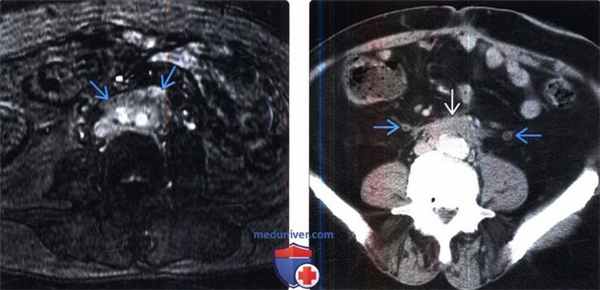

(Слева) МРТ, постконтрастное Т1-ВИ, режим подавления сигнала от жировой ткани: у этого же пациента визуализировано мягкотканное образование с высоким контрастным насыщением, которое окружает бифуркацию подвздошных сосудов, что соответствует активному фиброзу.

(Справа) КТ с контрастированием, аксиальная проекция: слой соединительной ткани, окружающий переднебоковые поверхности аорты и нижней полой вены. Этот слой стал причиной медиального смещения и умеренной дилатация обоих мочеточников.